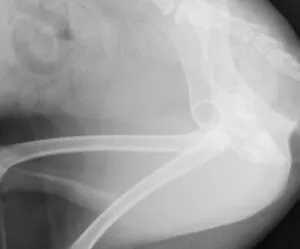

バンデージ固定により、歩行時の後肢可動域を制限しています。

2週後にバンデージを外しましたが、股関節は外れずに機能していました。